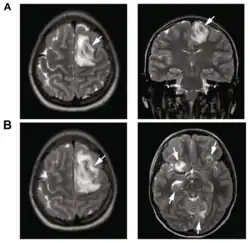

.png)

B: T1-weighted MRI showing expansion of the brain infection 4 days later